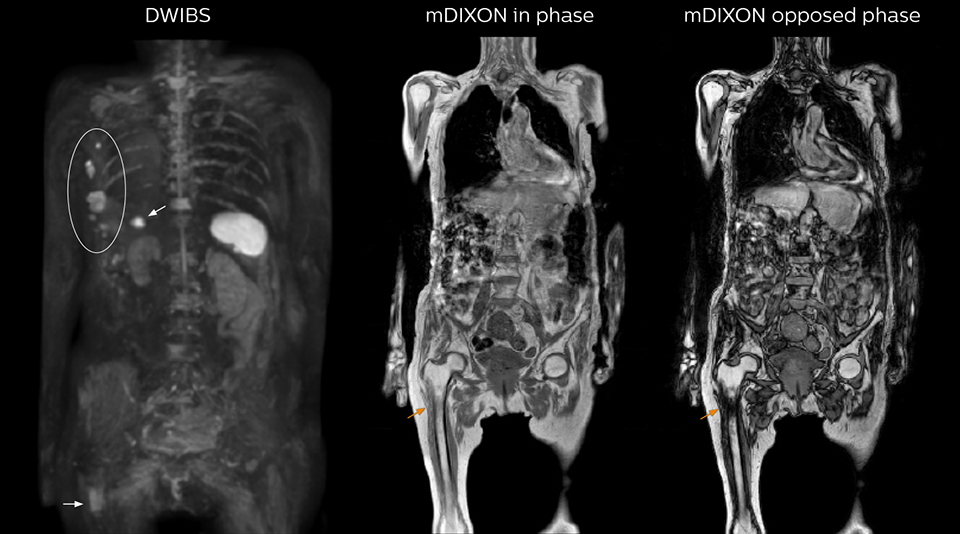

Radiologist Hiroshi Nobusawa, MD, PhD, explains that the coronal DWIBS protocol for whole body DWI is excellent for visualizing lesions in oncology patients. “About 90% of the DWIBS exams are done in this type of patients. The remainder of DWIBS exams are performed to gain information in cases of fevers of unknown origin,” he says. in image acquisition and postprocessing algorithms.”“mDIXON TSE sequences allow simultaneous characterization of morphological changes from the in-phase T2-weighted images and visualization of edematous changes, thanks to the water T2-weighted images from the same acquisition. Anatomical and morphological considerations could be a partial or complete ligament tear, a bony avulsion or hematoma.” “For soft tissue assessment mDIXON brings similar benefits. For example in one T2-weighted mDIXON TSE acquisition, having the multiple contrasts helps us assess abnormalities in peripheral nerves fascicles, which may be due to anatomical or inflammatory changes..” “In peripheral joints, we get good image quality in difficult areas with mDIXON TSE. Fat suppressed images appear homogeneous over the entire image, even with large coverage at 3.0T – for instance in scapular or hip girdles – or in the bearing areas or around metal prostheses*, where fat suppression is often deficient with STIR or spectral fat suppression, causing diagnostic difficulties. If a diagnostic image is right the first time, we don’t need to repeat or add a sequence.” “mDIXON TSE sequences allow simultaneous characterization of morphological changes from the in-phase T2-weighted images and visualization of edematous changes, thanks to the water T2-weighted images from the same acquisition. Anatomical and morphological considerations could be a partial or complete ligament tear, a bony avulsion or hematoma.” “For soft tissue assessment mDIXON brings similar benefits. For example in one T2-weighted mDIXON TSE acquisition, having the multiple contrasts helps us assess abnormalities in peripheral nerves fascicles, which may be due to anatomical or inflammatory changes..”

“The DWIBS sequence’s value in oncology cases is due to the high contrast it creates between lesions and surrounding tissue. Whole body DWI is requested by physicians who need to clarify TNM staging or determine therapeutic strategies, oncologists in need of diagnosis or follow-up scans, surgeons who need to see the presence of distant lesions that are sometimes difficult to detect by CT before surgery, and urologists for the evaluation of bone lesions, and the effect of chemotherapy and radiotherapy.”

“When we limited the scan coverage to the area from neck to femur, we could fit more clinical information in approximately the same scan time. So, we added coronal mDIXON, sagittal T1-weighted, and sagittal STIR sequences to our examination, instead of performing only axial DWIBS and coronal single-shot TSE scans.” The single shot T2-weighted TSE images are used for morphology and compared to DWIBS images to identify T2 shine-through. Sagittal STIR images are used in patients with inflammation or bone metastasis.

“mDIXON FFE allows us to quickly get information we need to assess the presence of fat. That gives us more information when we need to diagnose bone lesions, and when we are asked to judge fat-containing lesions such as hepatocellular or renal carcinoma,” Dr. Nobusawa says. “The mDIXON fat images can help us to differentiate fatty bone marrow from bone lesions. This is especially useful in elderly people, who tend to have fattier bone marrow. The water images provide a high signal-to-noise ratio in the intestinal canal, which is valuable for visualizing lesions in the colon,” he says.

Kawasaki Sawai Hospital’s whole body protocol also includes an mDIXON FFE sequence. Because mDIXON provides images for four contrast types – water only, fat only, in-phase and out-of-phase – from a single acquisition, it is useful in many ways.

“In-phase and out-phase sagittal T1-weighted FFE images help us to visualize and further characterize bone lesions such as metastasis and bone-marrow hyperplasia that have high signal on DWI. These images are also used throughout radiotherapy, to monitor changes in the fatty bone marrow.”